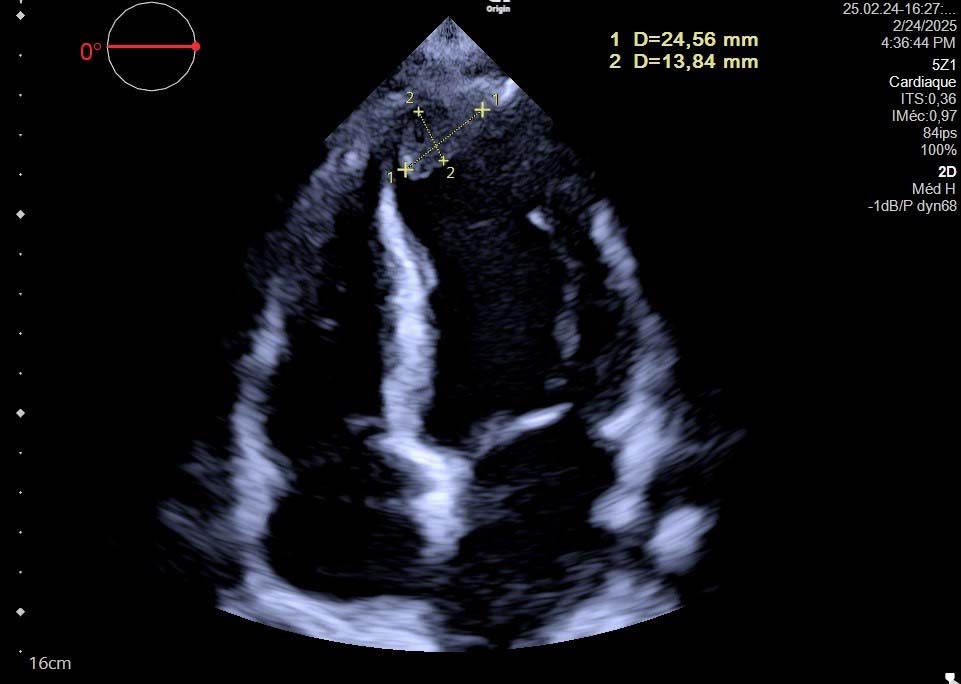

Fig. 1. Transthoracic Echocardiography - Apical Four-Chamber View Showing Left Ventricular Apical Thrombus. Two-dimensional echocardiography demonstrates an echogenic mass at the left ventricular apex (measured dimensions: 24.56 mm

Three-dimensional echocardiography has refined mass assessment by providing volumetric reconstructions with 62% better spatial resolution than standard 2D imaging. Recent studies reported that 3D-TTE modified the diagnosis in approximately 25% of cases and significantly impacted surgical planning over one-third of patients with pedunculated tumors by accurately defining attachment points and spatial relationships [13]. This technique demonstrated 95% concordance with surgical findings regarding tumor attachment sites, compared to 76% for 2D-TTE.